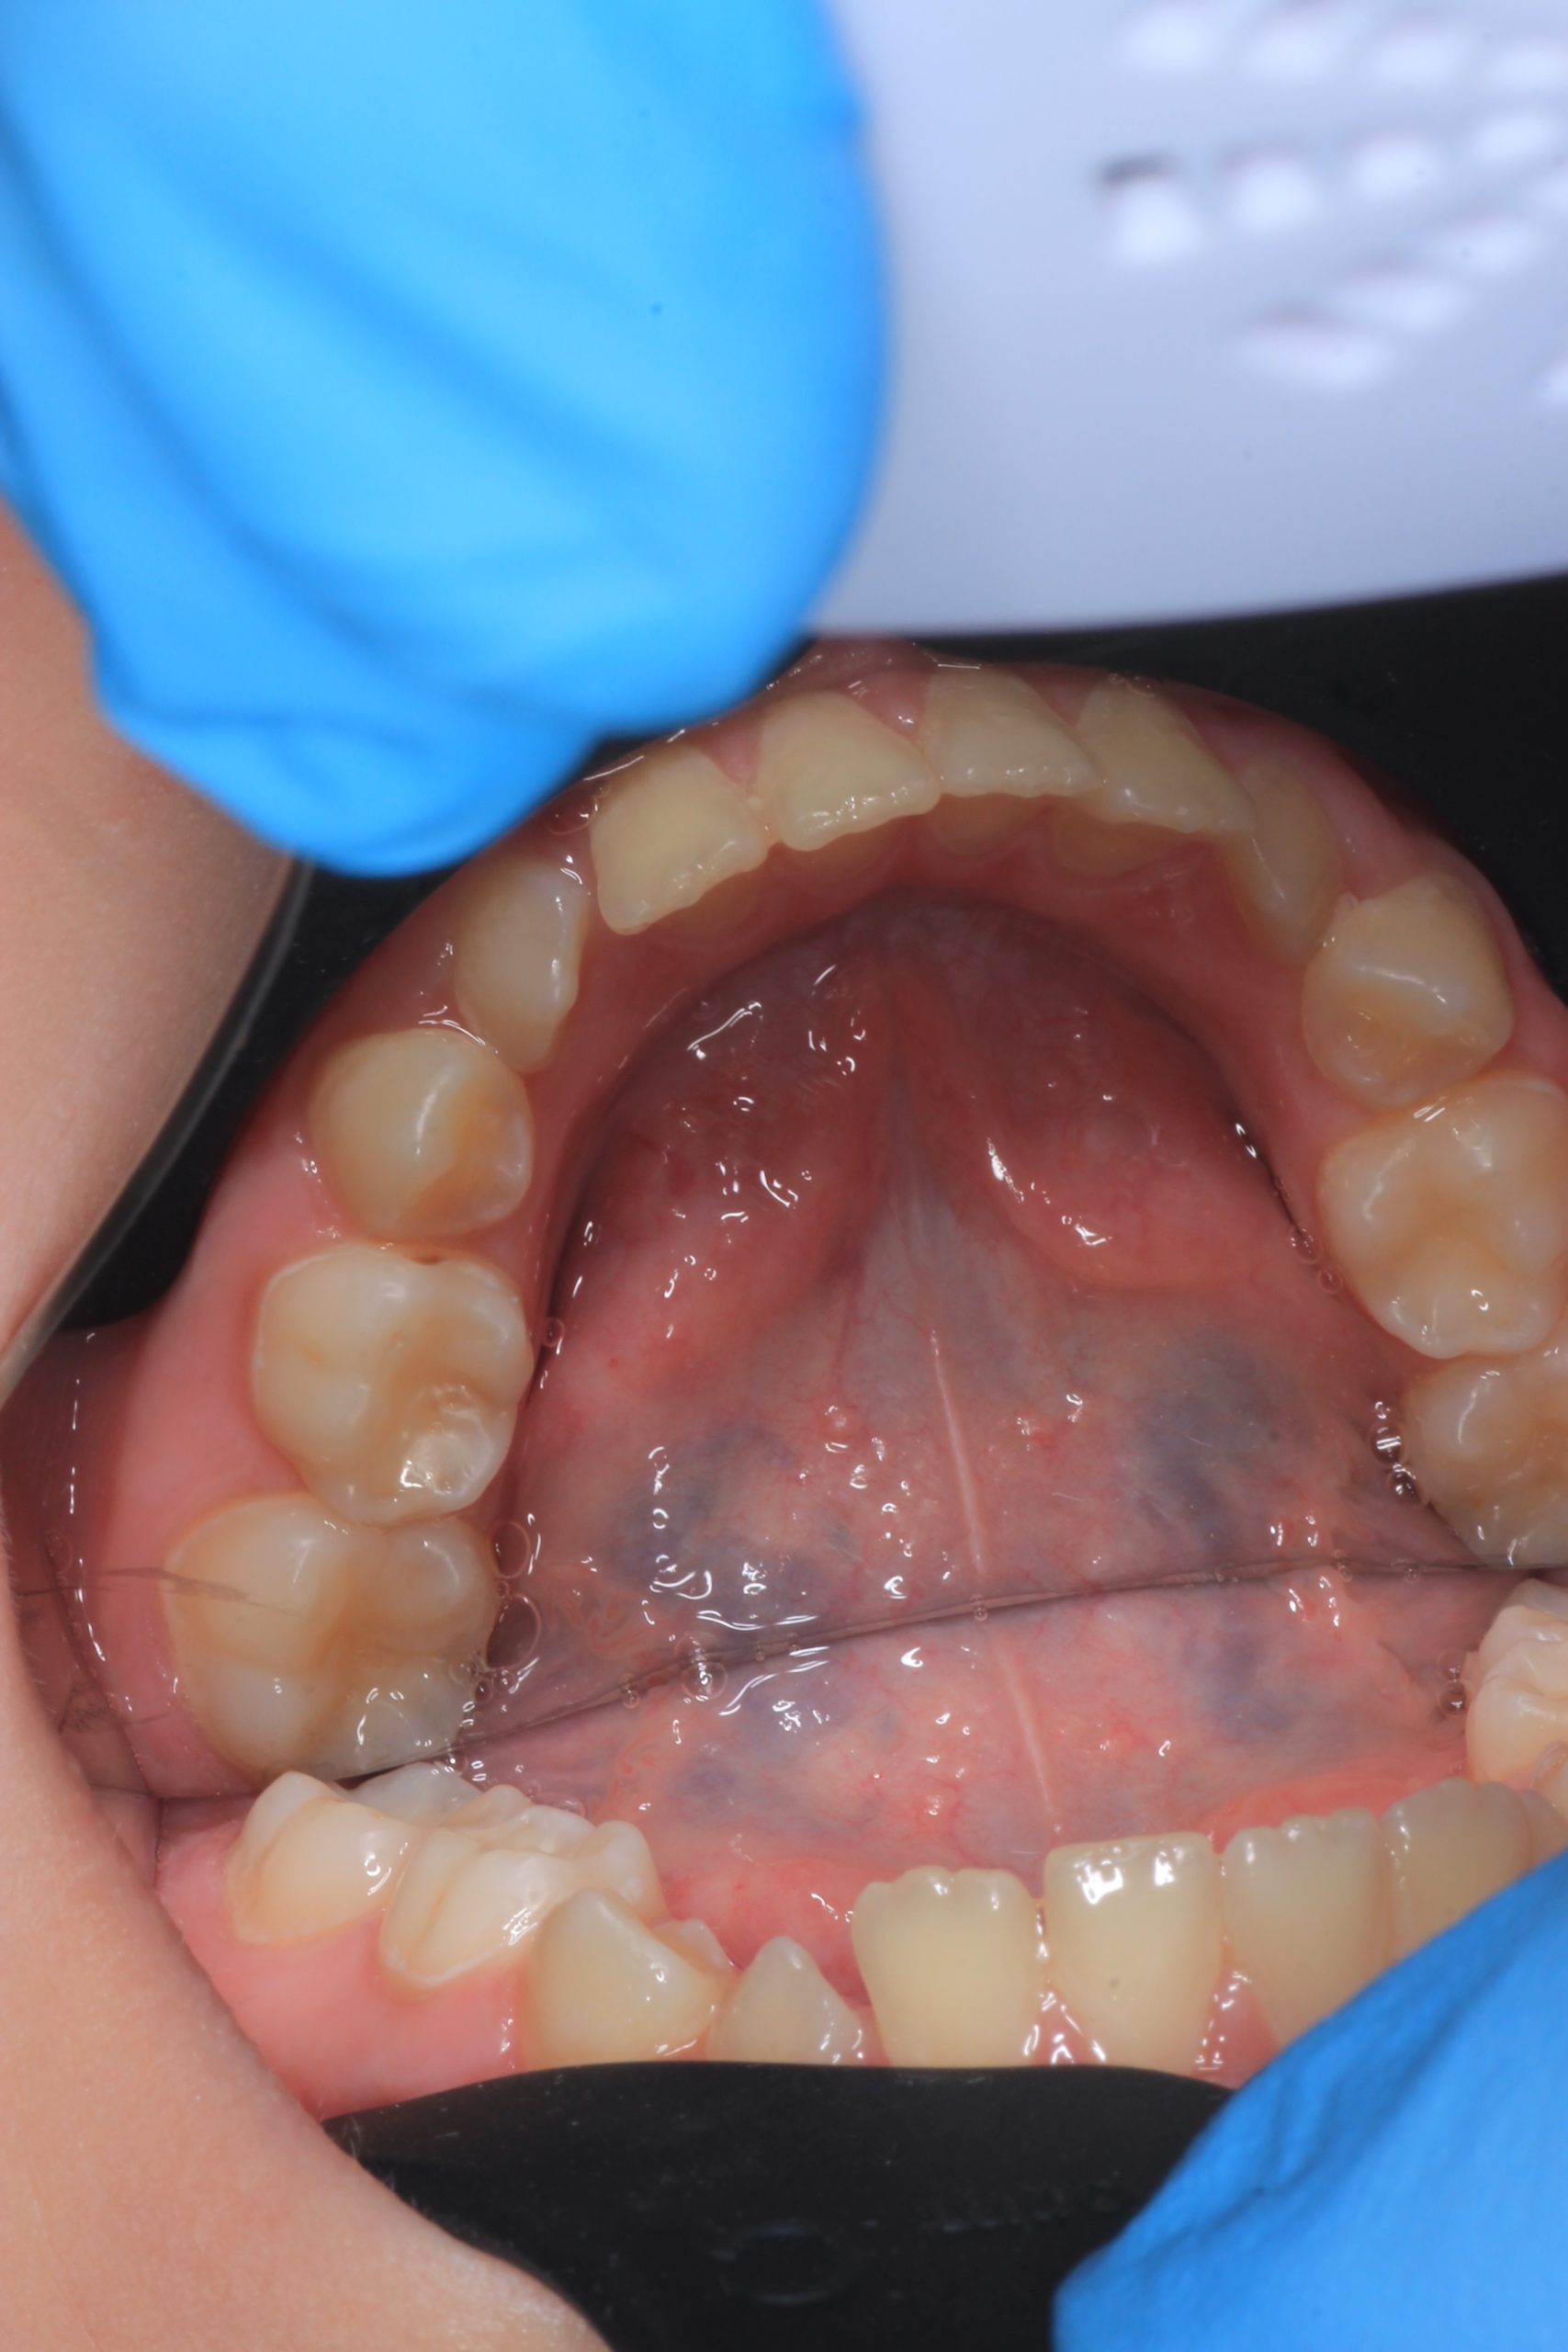

From age 4–5 and up, we perform full GBT cleaning using an ultra-fine erythritol powder to clean even hard-to-reach areas gently and safely. It does not damage enamel and is ideal even around braces — no need to remove brackets or wires. - Tartar Removal (If Needed)

Any tartar is removed gently and painlessly. - Final Check-Up + Fluoride Protection

We ensure the teeth are clean and free from early caries (even in the spot stage), then apply fluoride varnish to protect and strengthen enamel. - Personalized Recall Plan